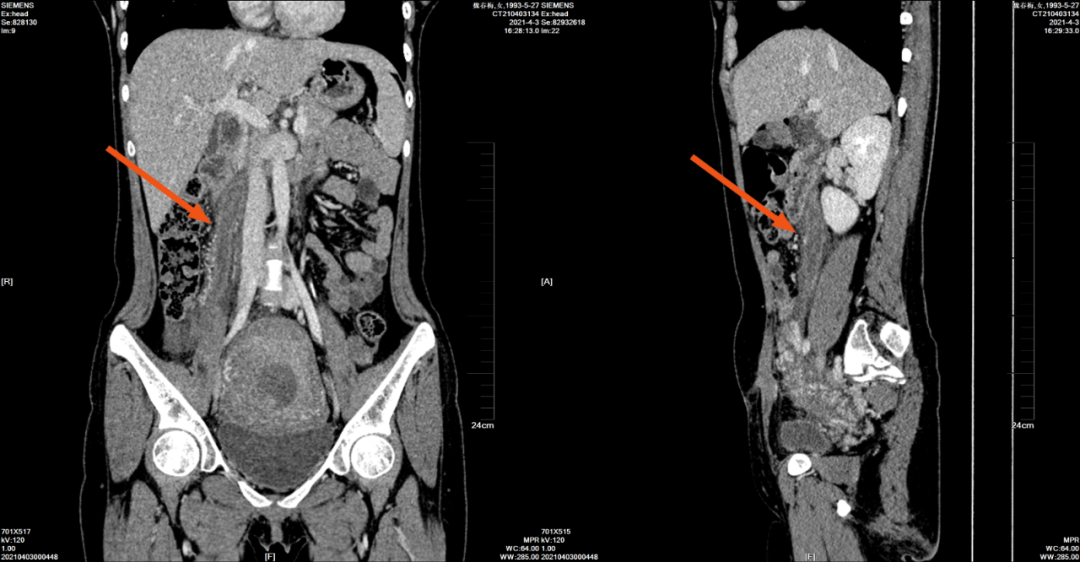

2021-4-3 中腹部+盆腔 CT 平扫如下:

右肾门平面(下腔静脉旁)至右侧附件区可见管状密度不均匀增高影,病灶边界不清,周围脂肪间隙模糊、密度增高,临近系膜增厚。

2021-4-3 腹部 CT 增强如下:

冠状位与矢状位

右侧卵巢静脉明显增粗,病灶自右侧卵巢静脉汇入下腔静脉处管腔内至右侧附件区可见不规则充盈缺损,右侧卵巢静脉周围可见条片稍低密度影。

(注:箭头显示右侧卵巢静脉血栓,其上端延续至下腔静脉内)